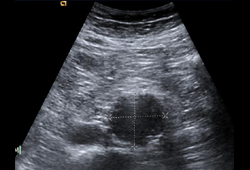

- abdominal ultrasound